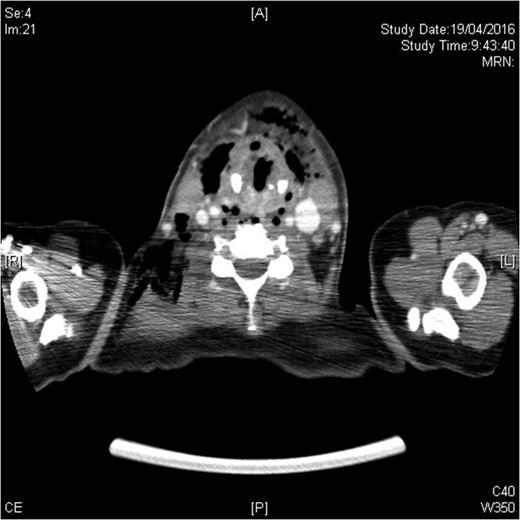

The urgent contrast computed tomography neck and thorax revealed multiple gas locules in bilateral deep cervical spaces, loculated right pleural effusion and right chest wall subcutaneous emphysema. The overall radiological features were suggestive of underlying deep neck space infection by gas-forming organisms complicated with descending mediastinitis and empyema thoracis (see Figs 1–3).

Infection extending down to superior mediastinum and chest wall.